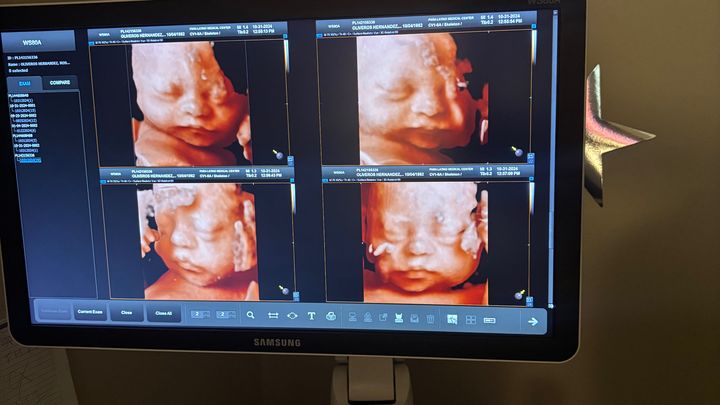

Today, I’m starting this fund in hopes of being able to get some help to pay off what has tragically happened to my mother to start 2025. Unfortunately, she found out on January 1 that the baby boy “Daniel Alejandro “ she was expecting had suddenly passed due to his heart-stopping. Being only a few days from coming into the world, Daniel wasn’t able to experience coming into the world to a fantastic woman of a mother, my mom Rosa. She had to deal with the pain of labor and suffering, but she knows that

We are incredibly heartbroken, but we know God has a place for him in heaven. He was such a smiling baby boy, and it’s painful not being able to help my mother raise another kid. My three younger siblings and I know we will have Daniel's blessings forever.

Hoy, estoy iniciando este fondo con la esperanza de poder obtener algo de ayuda para pagar lo trágico que le pasó a mi madre para comenzar el 2025. Desafortunadamente, ella se enteró el 1 de enero que el bebé “Daniel Alejandro” que estaba esperando. había pasado repentinamente debido a que su corazón se detuvo. A solo unos días de venir al mundo, Daniel no pudo vivir la experiencia de venir al mundo de la mano de una fantástica mujer de madre, mi mamá Rosa. Tuvo que lidiar con el dolor del parto y el sufrimiento, pero sabe que Estamos increíblemente desconsolados, pero sabemos que Dios tiene un lugar para él en el cielo. Era un bebé muy sonriente y es doloroso no poder ayudar a mi madre a criar a otro niño. Mis tres hermanos menores y yo sabemos que tendremos las bendiciones de Daniel para siempre. Recurrimos a nuestra comunidad en busca de apoyo durante este momento difícil. Mi mamá siempre ha sido la que tiende una mano y ahora te pedimos tu amabilidad y generosidad para ayudarla a cambio. Cualquier donación, por pequeña que sea, irá directamente a los gastos del funeral.